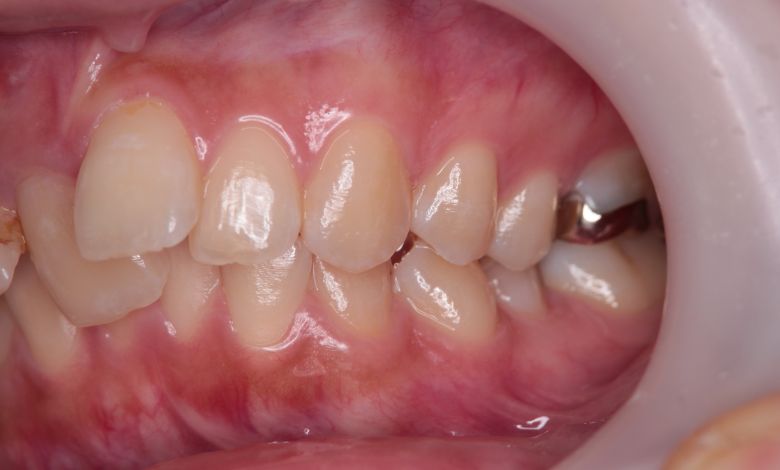

上下顎ともに犬歯が唇側に大きく突出しており、歯列弓が狭小なため、

他院では上下左右4本の便宜抜歯を前提とした矯正治療を提案されていました。

上顎には左右の犬歯が著しく唇側に偏位している

精密検査の結果、当院では抜歯を行わず、歯列弓の拡大によってスペースを確保し、非抜歯での矯正治療を選択しました。歯列の叢生(ガタガタ)は解消され、機能的かつ審美的に優れた咬合が得られました。